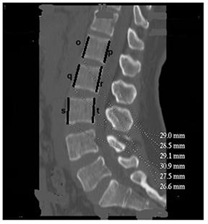

Figure 4. Sagittal section of the lumbar spine passing through the pedicles (beta angle). w: tangent to the upper plate of the vertebral body; x: axis of inclination of the vertebral pedicle on the horizontal; β: angle of inclination of the pedicle axis with respect to the horizontal plane.

The length of the pedicle decreased from L1 to L5 and there was no significant difference between the left and the right or between the man and the woman (p = 0.1). Pedicle width increased from L1 to L5 and was the same between left and right. Values in men were significantly higher than in women (p ˂ 0.001). The alpha angle increased from L1 to L5 (Figure 3). There was no significant difference between the left and right or between the man and the woman (p = 0.07). The beta angle (Figure 4) decreased from L1 to L5. The difference between the man and the woman was not statistically significant (p = 0.3).

Thus in our series, the length of the pedicle decreased from L1 to L5 and there was no significant difference by sex or vertebral side. The width, unlike the length, increased significantly from L1 to L5. There was no significant difference between left and right. However, it was greater in men than in women. The alpha angle of inclination of the pedicle axis with respect to the sagittal plane became more and more obtuse from L1 to L5. There was no significant difference between left and right or between the man and the woman. As for the angle beta of the axis of the pedicle with respect to the upper plate of the vertebral body, it became more and more acute from L1 to L5 and varied on average from 14.2 degree in L1 to 8.8 degree in L5. The difference between the man and the woman was not statistically significant although the values in humans seem smaller.